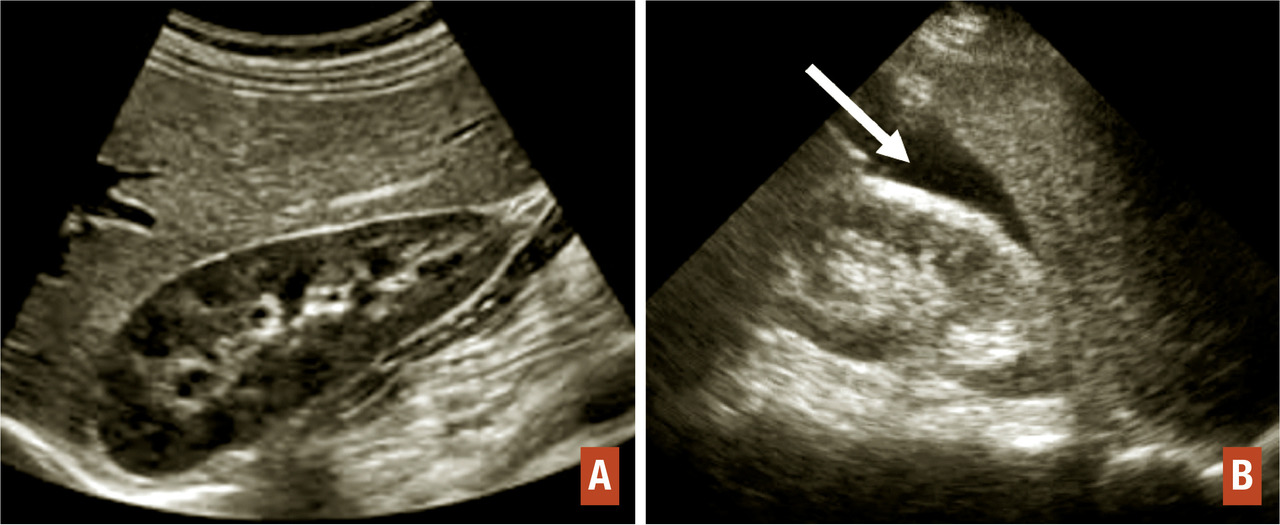

Elle constitue l’examen clé du diagnostic. Elle doit être réalisée par voie abdominale, puis par voie endovaginale à vessie vide. L’espace de Morrison situé entre le foie et le rein droit doit être systématiquement examiné par voie abdominale. La présence d’un épanchement dans cet espace signe la présence d’un hémopéritoine abondant (fig. 2).